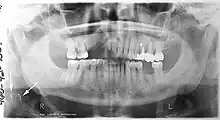

![]() A dental panoramic radiograph, showing the maxilla and mandible, all the teeth including the "wisdom teeth," the frontal and maxillary sinuses, the nasal cavity and the temporomandibular joint and other near by head and neck anatomy. | |

A panoramic radiograph is a panoramic scanning dental X-ray of the upper and lower jaw. It shows a two-dimensional view of a half-circle from ear to ear. Panoramic radiography is a form of focal plane tomography; thus, images of multiple planes are taken to make up the composite panoramic image, where the maxilla and mandible are in the focal trough and the structures that are superficial and deep to the trough are blurred.